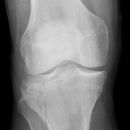

Gonarthrose

Es wurden keine Bilder gefunden.